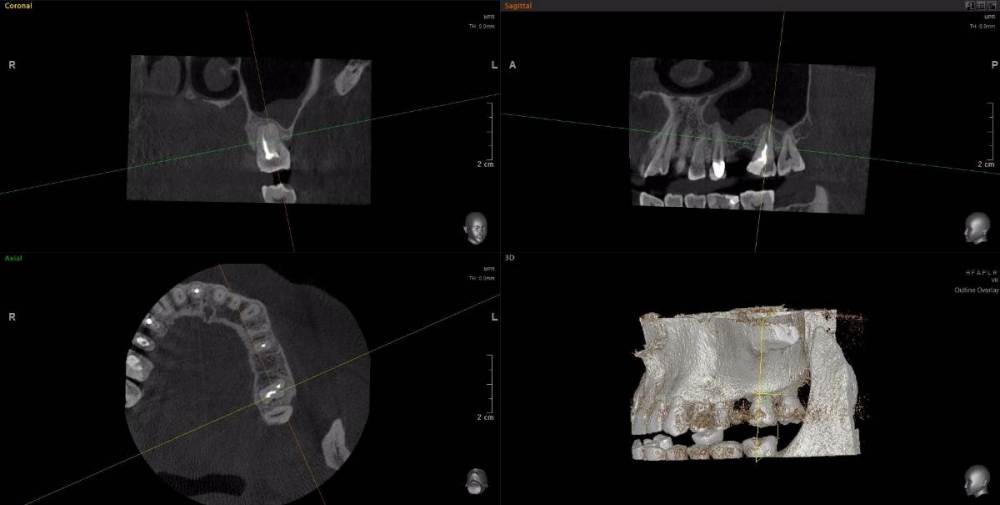

wladdX Опубликовано 15 апреля, 2021 Поделиться Опубликовано 15 апреля, 2021 Несколько скриншотов из вашей КЛКТ. Зуб 25: Зуб 27: Правая сторона: 1 Ссылка на комментарий

red_butler Опубликовано 16 апреля, 2021 Поделиться Опубликовано 16 апреля, 2021 1.5 1.6 перелечивать, 2.4 похоже кариес корня, нужно смотреть очно, 2.5 парадонтологическое поражение, смотреть очно, 2.6 ревизия корневых каналов Ссылка на комментарий